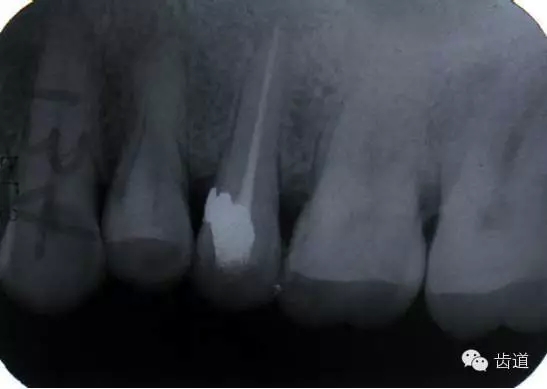

左上7近中頰根器械折斷

右上6腭根器械折斷

折斷于根管內(nèi)的器械要盡量取出,若無(wú)法取出經(jīng)常規(guī)充填后,成功率不受明顯影響。

1.折斷器械有一部分露在根管口外,用鑷子或持針器夾取出。

2.器械斷端在根管口內(nèi):用超聲根管銼在該器械旁增隙,通過(guò)超聲震蕩和沖洗,可將折斷器械從根管內(nèi)震動(dòng)沖出。在手術(shù)顯微鏡下直視操作,大大提高了取出的成功率。

3.折斷器械尖端已超出根尖孔:無(wú)癥狀不處理;有疼痛則作根尖手術(shù)取出。